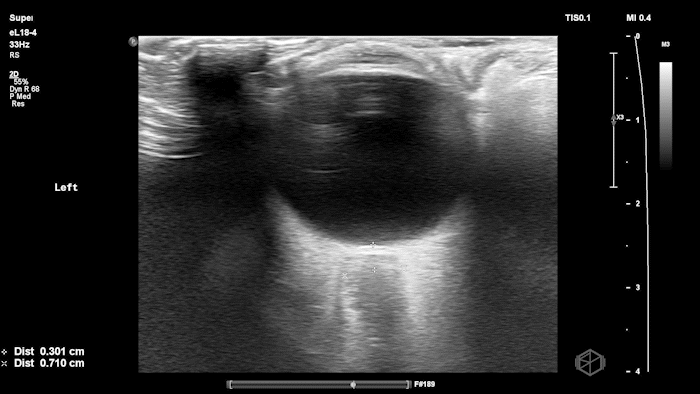

They were examining a 30’s female who was presenting to the ED with headaches for multiple years and had some vision disturbances. The performed an ocular POCUS that demonstrated the following:

The POCUS shows optic nerve edema right (0.793cm) greater than left (0.71cm) with bilateral papilledema. There may also be a faint vitreous detachment of the right eye. There was concerned for increased intracranial pressure.

The patient had an MRI brain and orbits that showed, “intraocular protrusion of the right greater than left optic nerve heads with increased prominence of the CSF spaces of the bilateral optic nerve sheaths, can be seen in a idiopathic intracranial hypertension.” She had a lumbar puncture that had elevated opening pressure and was started on acetazolamide.

Diagnosis: Bilateral optic nerve edema/papilledema and idiopathic intracranial hypertension

ONSD measurements in this case are markedly abnormal. The optic nerve sheath diameter (ONSD) is measured 3 mm posterior to the globe. In adults, an ONSD > 5.0 mm is generally considered abnormal; values > 6.0 mm are strongly associated with raised intracranial pressure (ICP). Bilateral measurements of 7.9 mm (right) and 7.1 mm (left) are consistent with elevated ICP. The probe should be held lightly with ample gel to avoid artifactual compression (📚 PMID: 18509619, 18275454)

Point-of-care US measurement of optic disc elevation/height helps when fundoscopy is limited. Studies report cutoffs from ~0.6–1.0 mm: ≥1.0 mm is highly specific for papilledema in ED cohorts; lower cutoffs (≈0.6–0.7 mm) improve sensitivity. (📚 PMID: 24050798, 37227512)